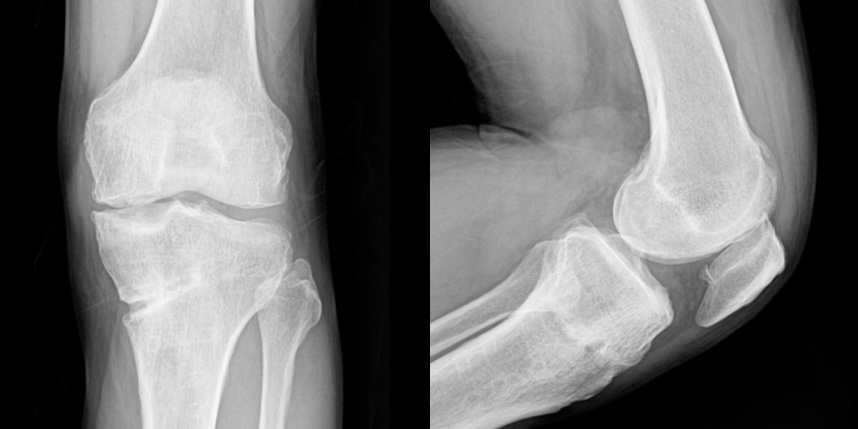

연골손상의 단계를 결정할 때 사용하는 ICRS 단계에서 3단계 미만의 연골손상에 사용하는 방법으로 울퉁불퉁한 표면을 다듬어 주는 정도의 수술법입니다.

4단계 이상일 경우 미세천공술을 기본으로 시행하며, 미세천공술로 나온 본인의 골수줄기세포와 함께

연골 생성을 촉진할 수 있는 “재료”를 같이 주입하는 치료를 시행합니다.

손상된 연골 부위에 작은 구멍을 뚫어 골수에서 나오는 줄기세포를 이용하여 연골 재생을 유도하는 방법으로 근본적으로 섬유연골(정상연골보다는 약한 연골)로 재생된다고 알려져 있습니다.

특수하게 농축하여 제작된 6% 콜라겐(리젠실603) 또는 9% 콜라겐(이엔카티)을 천공술을 시행한 부위에 덮어 주어 미세천공술 단독보다 좋은 치료 결과를 기대할 수 있습니다.

환자 자신의 건강한 연골을 채취하여 손상된 부위에 이식하는 방법으로, 발목 연골 손상에 주로 이용하며 정상 연골을 채취해야 하기 때문에 공여부(donor site)의 문제가 있을 수 있다는 점이 최대 단점입니다.